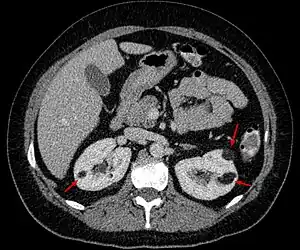

Angiomyolipoma in both kidneys (arrows) as seen on CT scan. The tumors are hypodense (dark) due to fat content. | |